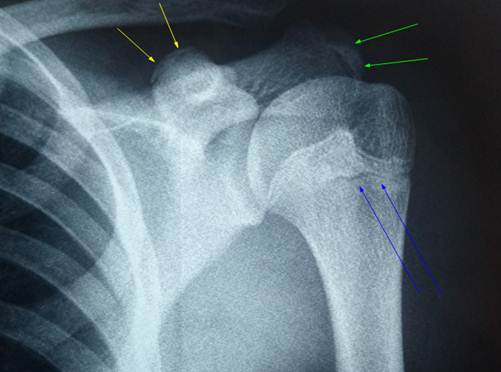

Снимок

проксимальной части плечевой кости юноши 17 лет, направленного на лечение с

диагнозом перелома шейки плечевой кости. Линия того, что приняли за перелом,

обозначена синими стрелками. Но это не перелом! Так специфично выглядит линия

зоны роста эпифиза плечевой кости, и сохряняется этот просвет порой до 20 лет.

Кроме того, на снимке отлично видны ядра окостенения верхнего изгиба

клювовидного отростка (желтые стрелки) и ядро окостенения верхушки

акромиального отростка (зелёные стрелки).